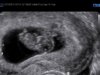

Huff, så ekkeltHer går det sånn passe[emoji4] Hadde litt blødning idag men skal heldigvis på ul på tirsdag[emoji173][emoji173] Ellers så krangler bekkenet litt og kvalmen kommer og går[emoji85] Men så lenge lille har det bra så skal jeg ikke klage[emoji4] Gleder meg til ul på tirsdag for å se at alt fortsatt er bra[emoji7]

Det er nok uskyldig, men godt du har ul på tirsdag så du får undersøkt det